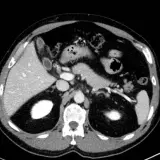

Over 2,100 interactive radiology cases, curated by radiologists for your level of training. Scroll, window, and view cases full screen — just like on PACS. Click linked findings in each writeup to jump straight to them on the image. Cases include sample reports, a focused discussion section, original illustrations, and videos.

PACSで期待されるツールを完備した完全インタラクティブな症例 — スクロール、ウィンドウ調整、ズーム、パン、計測、ROI、フルスクリーンモード。

重要な所見を症例画像上に直接ハイライトする豊富なアノテーション。症例解説内のリンクされた所見をクリックすると、スキャン上の正確な位置へジャンプできます。